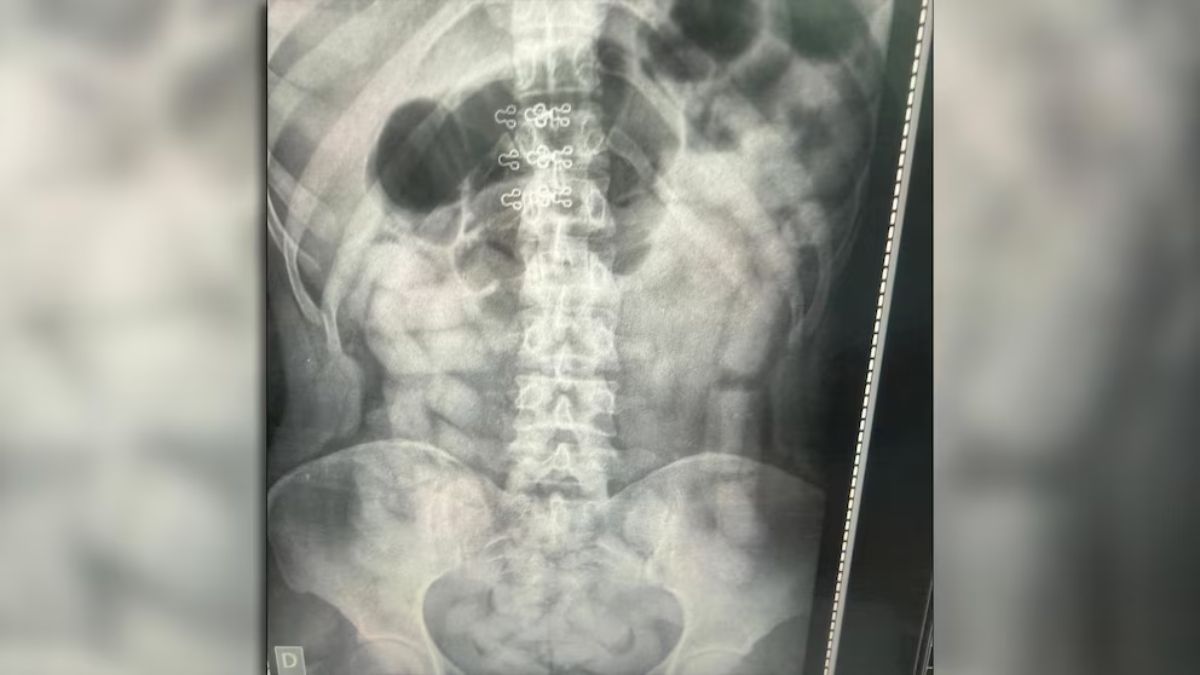

Radiografías de un peligro mortal

Bajo las órdenes del Juzgado Federal de Tucumán N° 2, los 53 pasajeros fueron trasladados para una revisión exhaustiva. A la mañana siguiente, las placas radiográficas confirmaron el peor escenario: cuatro mujeres y dos hombres tenían sus abdómenes repletos de cuerpos extraños.

Los involucrados fueron internados de inmediato en los hospitales de Santa Ana y Los Sarmientos. Allí, bajo estricta custodia médica y policial, expulsaron un total de 503 cápsulas. El riesgo de muerte por el estallido de un solo envoltorio es casi del 100%, pero en esta ocasión, el cargamento llegó a pesarse en su totalidad.